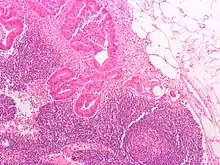

Micrograph of a colorectal adenocarcinoma metastasis to a lymph node. The cancerous cells are at the top center-left of the image, in glands (circular/ovoid structures) and eosinophilic (bright pink). H&E stain.